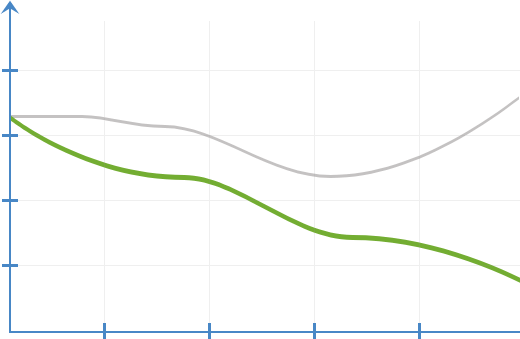

Dinamica schimbărilor

proceselor inflamatorii

fără Prostalisan

cu Prostalisan